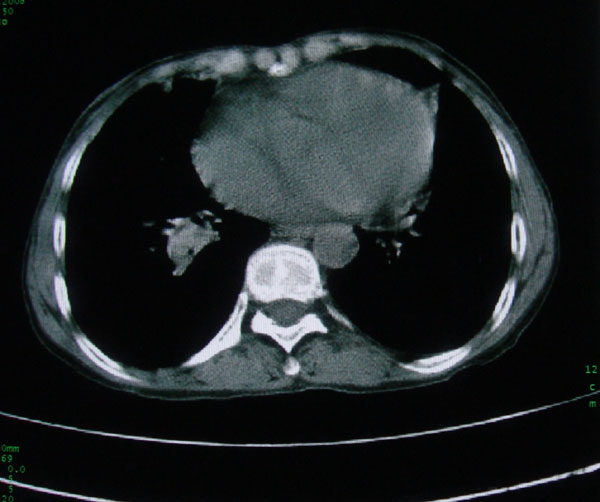

标题: CT15046:F59Y,咳嗽间断咳血丝痰就诊. [打印本页]

标题: CT15046:F59Y,咳嗽间断咳血丝痰就诊.

咳嗽\间断咳血丝痰就诊.

考虑支气管扩张并感染

1慢支伴感染;右下肺周围型肺癌。

本例应该是“慢性疾病并发多种合并症”即:慢支并感染并支气管扩张征!结合病灶分布 形态分析,不除外合并“继发性肺结核”!

慢性支气管炎伴全小型肺气肿、支气管扩张、感染、间质纤维化。

多考虑支气管扩张并感染,双下肺继发性肺结核不除外